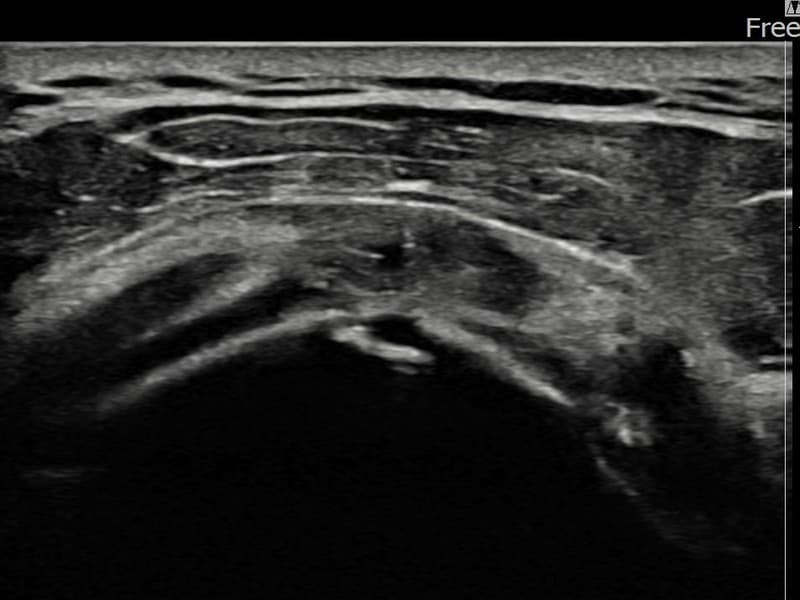

After

시술 전 초음파 측정 결과 파열 크기는 8mm × 3mm (힘줄 두께의 약 33% 결손)로 확인되었습니다. 시술 전 초음파에서 좌측 극상근건 관절면측의 에코 단절과 힘줄 내 저에코 결손이 확인되었습니다. 시술 후 초음파에서 파열 부위가 재생 조직으로 채워지고 힘줄 에코 패턴이 정상화된 것이 관찰되었습니다.

60대 중반 남성 환자분으로, 왼쪽 어깨 통증이 수개월간 지속되다가 최근 야간 통증까지 생겨 내원하셨습니다. 활동적인 생활을 즐기시는 분으로 통증으로 인해 운동이나 취미 활동에 제약이 생기셔서 비수술 치료를 강력히 원하셨습니다. 초음파 검사에서 좌측 극상근건 관절면측 부분파열이 확인되었으며, 초음파 유도 하 축소봉합술을 시행하였습니다. 시술 후 단계적으로 재활 운동을 진행하였고, 10주 후 추적 초음파에서 파열 부위가 재생 조직으로 채워지고 힘줄 연속성이 회복되어 정상 생활에 복귀하셨습니다.